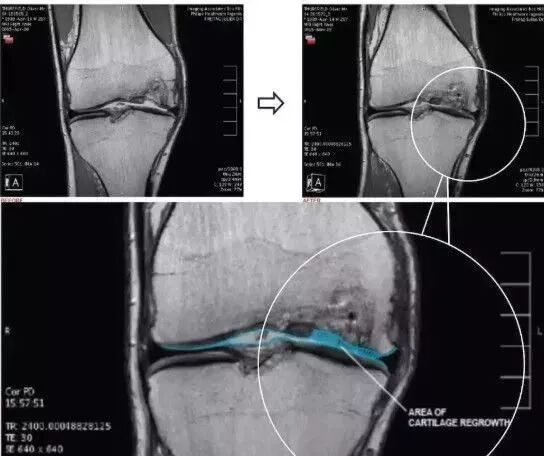

上海本正干细胞技术有限公司提供的干细胞是从脐带、胎盘中提取的一种修复器官机理的未完全分化的原始细胞,具有自我更新、多项分化和高度繁殖的能力,医学上称为“万能细胞”,它是形成人体各种组织器官的起源细胞。干细胞对临床上一些疑难疾病的治疗如:脑瘫、老年痴呆、脑萎缩、帕金森病、中风、肝硬化、糖尿病、红斑狼疮、股骨头坏死、软骨和关节损伤、心脏和脊髓损伤等,取得显著效果,它拥有更加鲜活细胞能量,可以快速、有效进入体内,分泌多种有益细胞因子,调节体内微环境,激活干细胞再生能力,重启时光之门,追溯青春绽放源头,实现对人体衰老状态减缓,同时有效改善身体亚健康以及预防肿瘤发生。